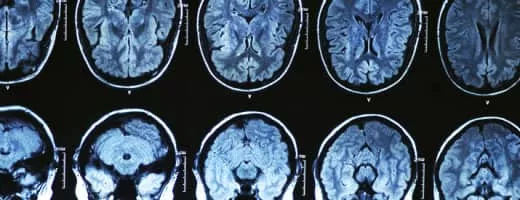

Neuroradiology is a subspecialty of radiology focusing on the diagnosis and characterization of abnormalities of the central and peripheral nervous system, spine, and head and neck using neuroimaging techniques.